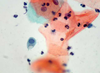

2

Q

A

2 Trichomonas vaginalis